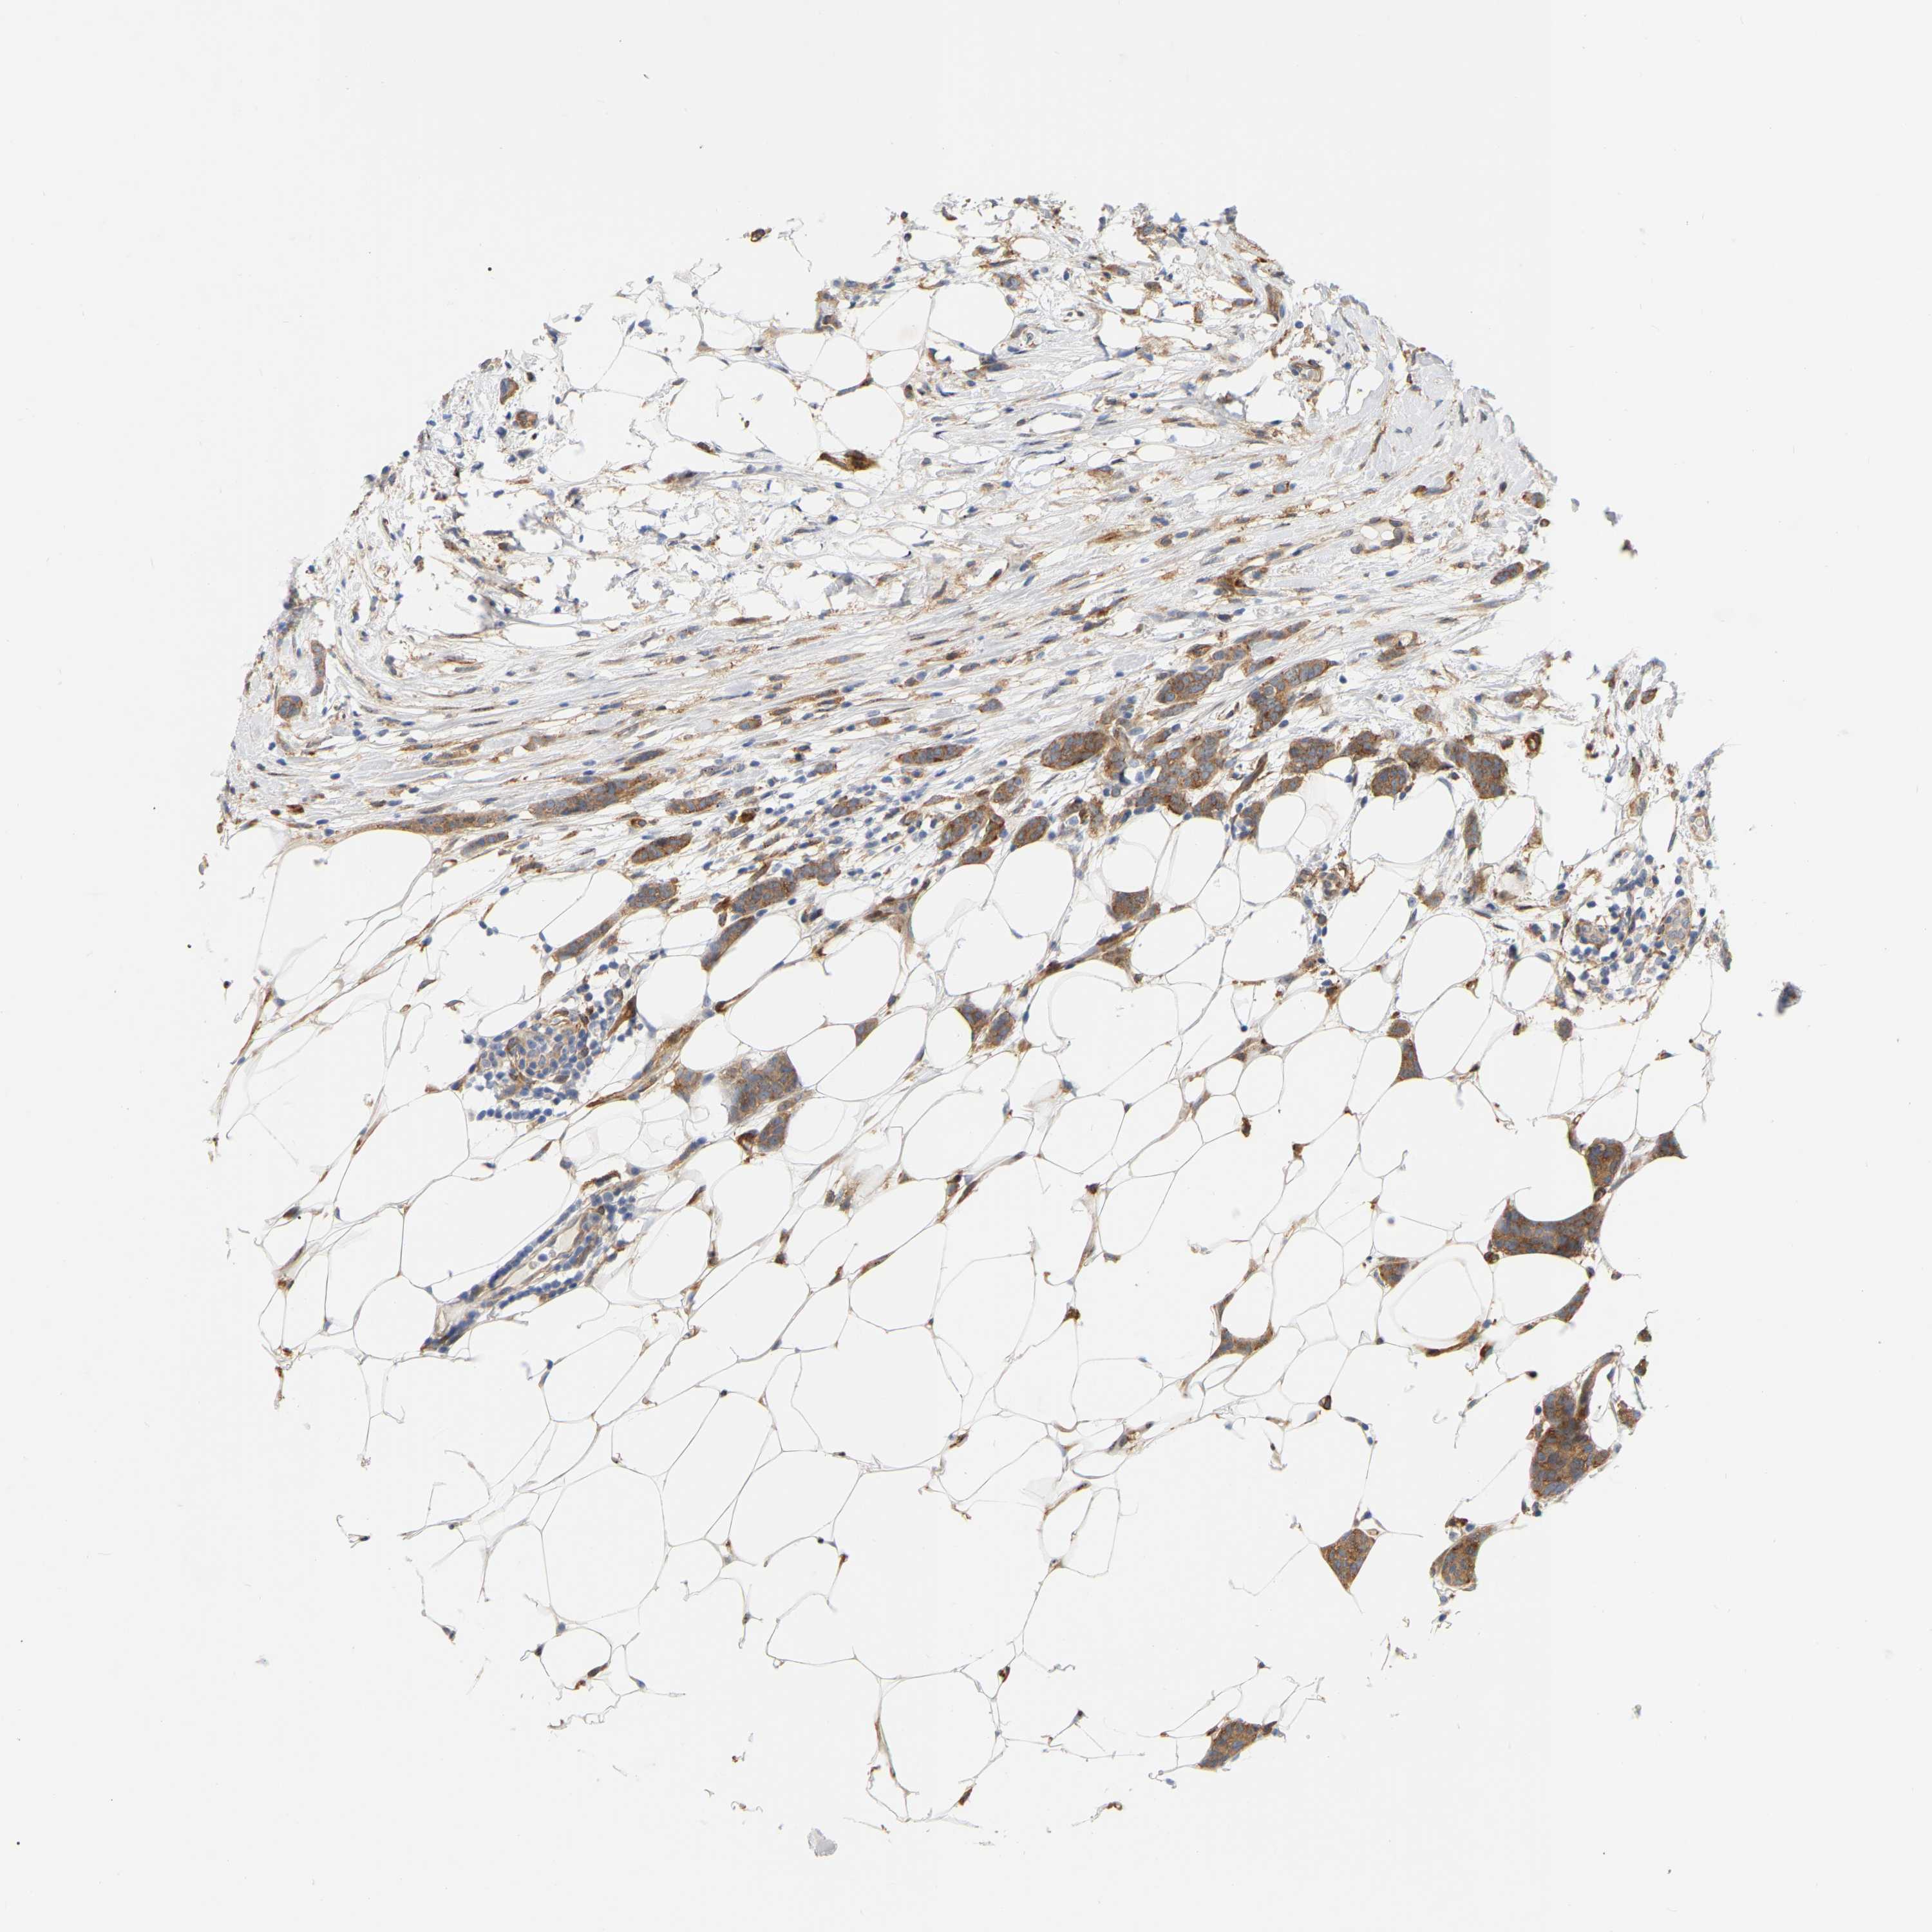

CANCER BREAST CANCER Show tissue menu

BRCA TCGA BRCA VALIDATION PROTEIN EXPRESSION

Breast cancer

Human cancer